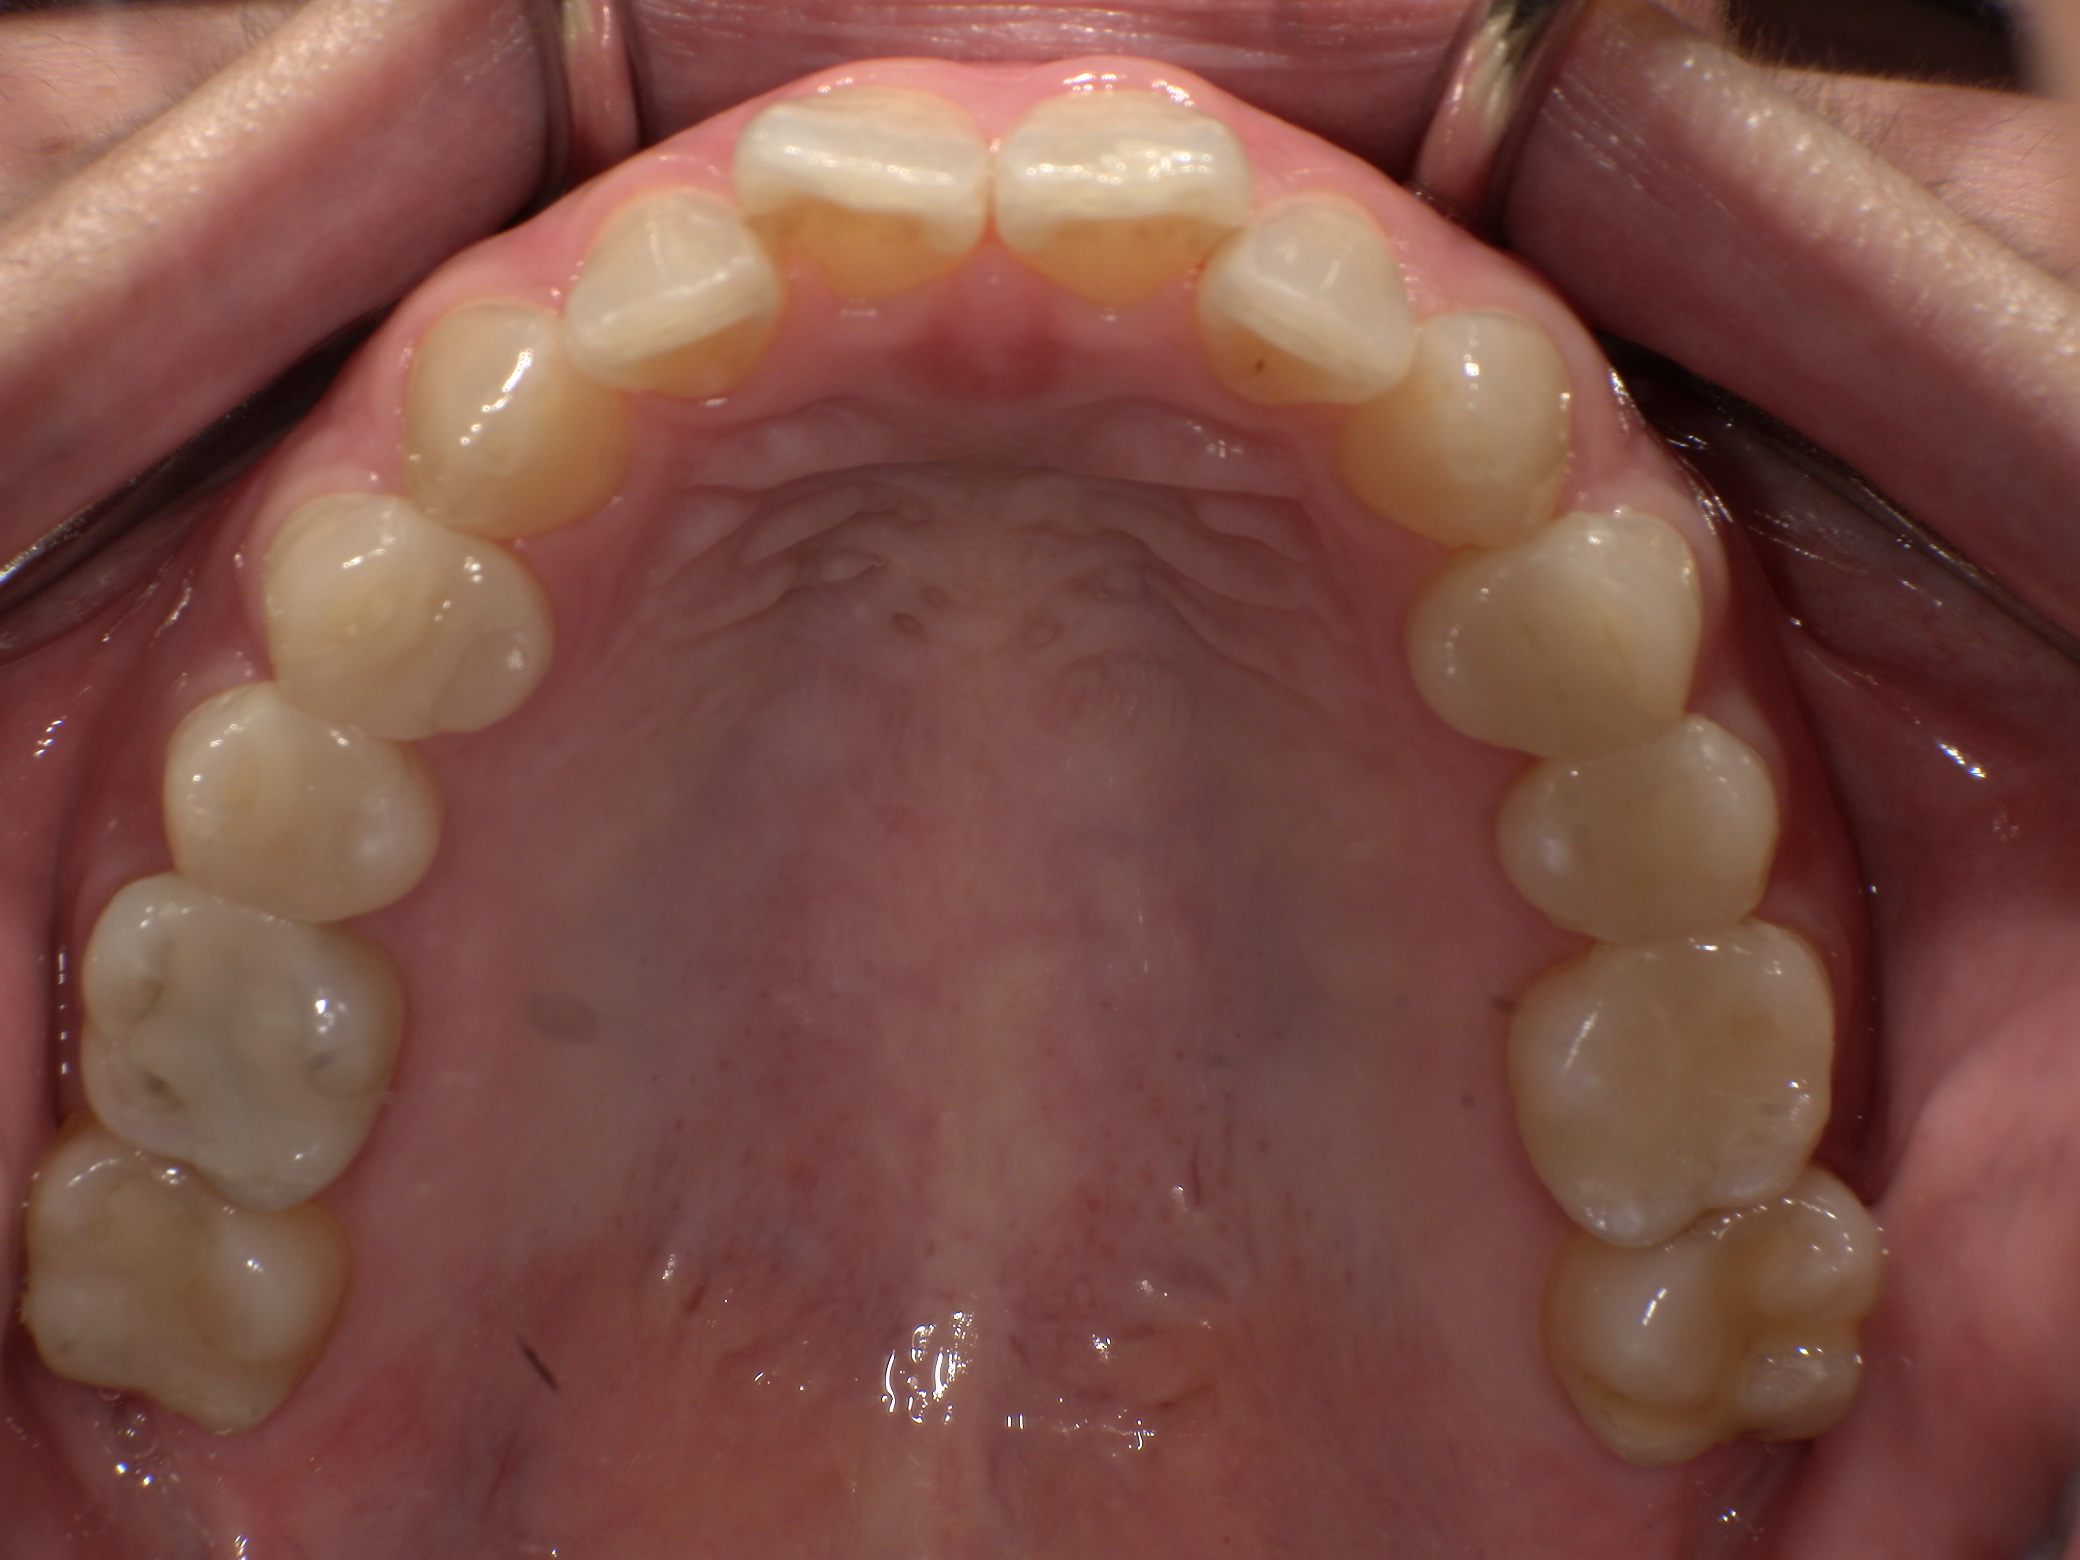

歯を失わないための歯周病治療

歯周病はサイレントキラーとも呼ばれ、自覚症状がないうちにどんどん症状が深刻化していく病気です。

大切な歯を失わないためにも、歯周病には早期発見・早期治療が大切です。

歯周病は、細菌感染によって歯を支えている歯肉・歯根・歯槽骨といった組織を破壊していく病気です。

始めは腫れや炎症程度から始まり、症状が進行していくと歯がグラグラと動揺し始め、最終的には歯が脱落してしまうこともあります。

虫歯と並んで歯を失う二大疾患とされています。